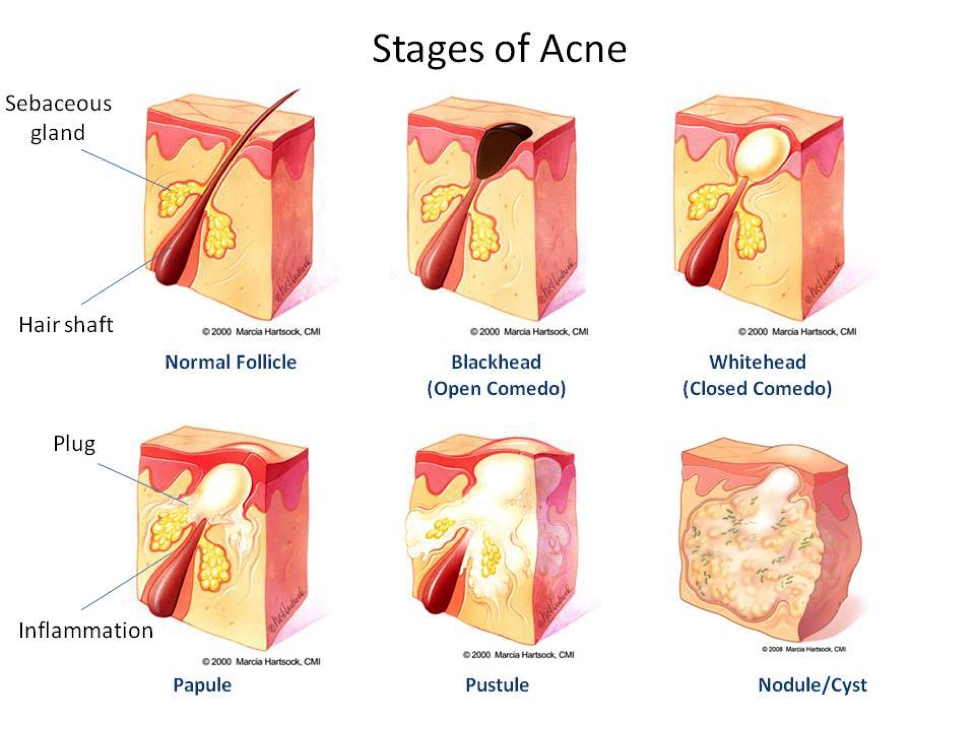

Acne comes in grades 1 to 5.

- Grade 1 (Mild): Generally associated with Open Comedones (blackheads), Closed Comedones (whiteheads), Papules (very few red bumps).

- Grade 2 (Moderate): More Comedones plus numerous Papules. Pustules (pus filled bumps) on specifically the face.

- Grade 3 (Moderately Severe): Usually associated with many Papules and Pustules with occasional inflamed Nodules (hard lumps under the skin) appearing often on the back and chest in addition to the face. When untreated, scarring can occur.

- Grade 4 (Severe): Painful and inflamed Pustules and Nodules extending to more areas of the body. More likely to cause scarring.

- Grade 5 (Very Severe/Nodulocystic): Highly inflamed and extensive acne with numerous large Nodules and Cysts (deep, pus-filled lesions). Highly scarring. Generally requiring medical intervention.

Delving beneath the skin's surface, we find a complex network of hair follicles intertwined with sebaceous glands. These glands make sebum, a natural oil that keeps our skin moisturised and supple.

However, various factors including hormonal changes, stress, and medications can stimulate these glands to induce excess sebaceous activity. When too much oil mixes with dead skin, it blocks pores and provides an ideal environment for bacteria to proliferate and the formation of acne symptoms.

Comedones & Enlarged Pores

Open Comedones (Blackheads) The characteristic black hue of these comedones isn't a sign of embedded dirt or grime. Instead, it's the result of oxidation reactions when the trapped oil and skin cells are exposed to the air.

Closed Open (Whiteheads) are pores that are completely sealed with a thin layer of skin, unlike blackheads. This seal stops oxidation, causing small, light-colored bumps that may feel slightly raised.

Papules & Pustules

Papules are small red, solid, and inflamed bumps on the skin that do not contain pus.

Pustules are infected papules that have accumulated pus, white or yellow, from bacterial activity.

Both are a result of from pores becoming clogged with oil and dead skin cells.

Nodules & Cysts

Nodules are firm painful lumps that feel deep in the skin that can be visible on the surface.

Cysts however are softer masses of accumulated pus appearing yellow and white. Rupture of cysts can cause more cysts to develop in the area and become scar inducing.

Nodulocystic cysts are severe, pus-filled, deep, and inflamed hard bumps combining the characteristics of nodules and cysts. These are painful on contact and are highly prone to scarring the skin.

All are caused from the build up of bacteria feeding off the oil and dead skin cells trapped under the surface skin.